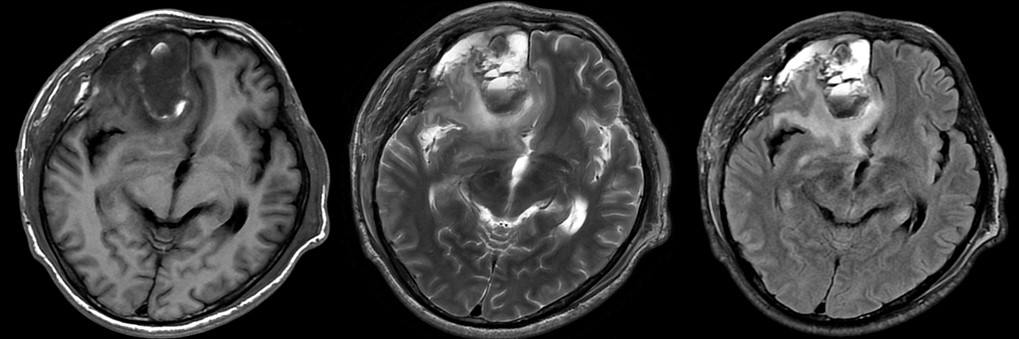

增强反映的是血脑屏障是否完整,患者做了手术,血脑屏障肯定是被破坏了,这时无法分辨是残余的肿瘤强化还是术后损伤。灌注可能给出答案,灌注反映的是组织的微血管分布和灌注情况,若有残余的肿瘤,则表现为灌注升高,正好我们在增强前做了不打药灌注3D ASL:

3D ASL显示病灶区低灌注,提示强化区为术后损伤,并不是残存的肿瘤。